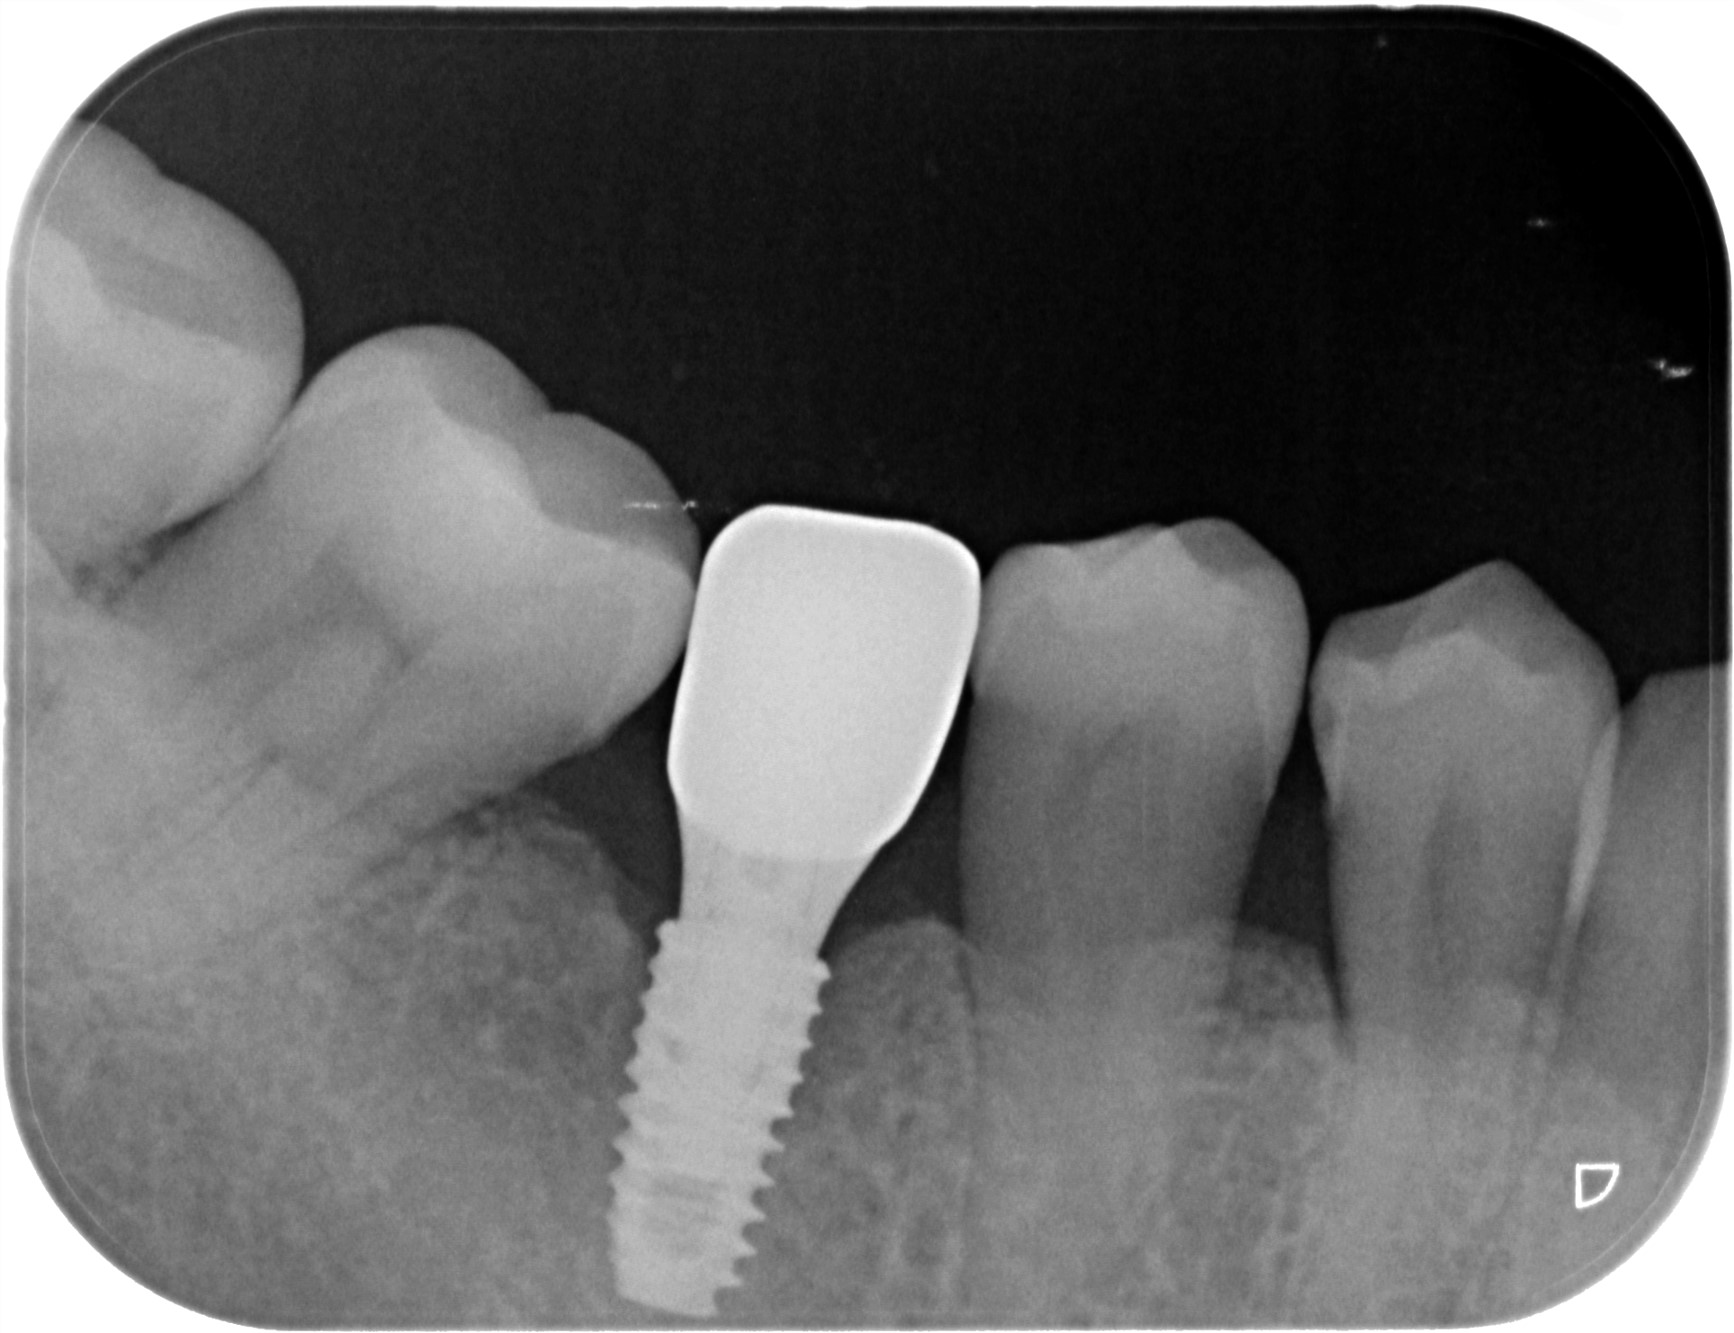

治療後

治療後レントゲン写真

- 治療名称

- 右下56番パーシャルデンチャー部のインプラント治療

- 患者の症状

- 60代女性 右下56番にパーシャルデンチャーを装着しており機能及び審美的に問題を抱えている。

- 治療内容

- まず、CT撮影による精密な骨の分析・治療計画を立てガイドを使いインプラント埋入しインプラントが骨と結合するのを待つ間に仮の歯を入れます。その後本歯を作成して装着しました。

- 治療期間・回数

- インプラント埋入からジルコニアセットまで三か月半

- 費用

※自由診療となります - ■総額:¥660,000(税込み) ■内訳:埋入(ガイド込み)¥200,000×2、仮歯¥20,000×2、被せ物¥80,000×2

- リスク・副作用

- ・術後の腫れ・痛み・出血 ・感染(インプラント周囲炎) ・インプラントの脱落 ・神経損傷によるしびれ ・破損・ゆるみ